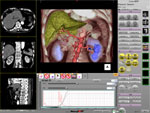

■ 大腸解析

大腸解析ソフトではCTのボリュームデータから胃や大腸を自動抽出し、オーバービュー画像(展開画像)からリアルタイム仮想内視鏡までをフルオート処理。仮想内視鏡にMPR画像を重ねた表示では壁内のみでなく、壁外情報を同時に観察することができます。 |